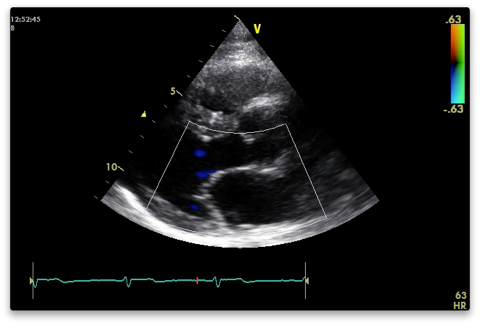

Colour (Nyquist limit 50-60 cm/s)

Aortic and mitral valves for stenosis and regurg. Do one at a time. The resolution is better the narrower and shallower you have the colour box (cutting off the near field makes no difference).

Measure vena contracta if present (narrowest width of regurg colour).

Colour M-mode for AR if present - measure jet width and calculate as percentage of LVOT width.

LVOT for flow acceleration if septal hypertrophy